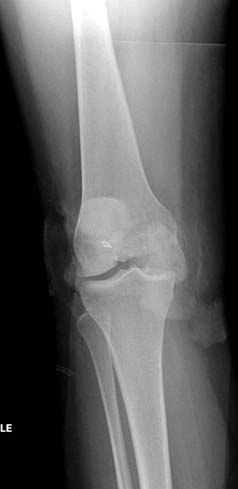

[Ortho] Нелеченный перелом Hoffa

Здесь представлены различные варианты фиксации перелома, а также снимки

комбинации перелома с повреждением хряща (12-19). Пластика хряща

OsseoFit и установка custom made plate.